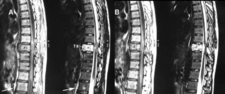

Tanı YöntemleriAtipik hemanjiomun tanısı genellikle görüntüleme yöntemleriyle konur. Bu yöntemler arasında:

Bu görüntüleme yöntemleri, hemanjiomun boyutunu, konumunu ve yapısını belirlemek için kullanılır. Ayrıca, doktorlar histolojik inceleme için biyopsi de alabilirler. Tedavi SeçenekleriAtipik hemanjiom tedavisi, hastanın genel durumu, tümörün boyutu ve belirtilerin şiddeti gibi faktörlere bağlı olarak değişiklik gösterir. Tedavi seçenekleri arasında:

MRG ve BT gibi görüntüleme yöntemleri tanı ve takipte oldukça güvenilirdir. Cerrahi müdahale genellikle sadece şu durumlarda gündeme gelir: şiddetli ağrı, nörolojik defisit riski, patolojik kırık tehlikesi veya hızlı büyüme. Mevcut tedavi seçenekleri arasında gözlem, embolizasyon, radyofrekans ablasyon ve cerrahi yer alır.